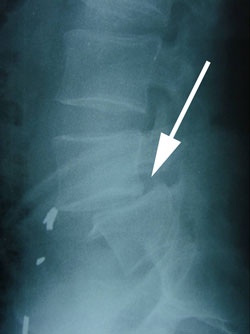

Spondylisthesis is the forward slipping of one vertebra (See arrow.), usually L5, upon the one below.

spondylolisthesis xray

xray of spondylolisthesis